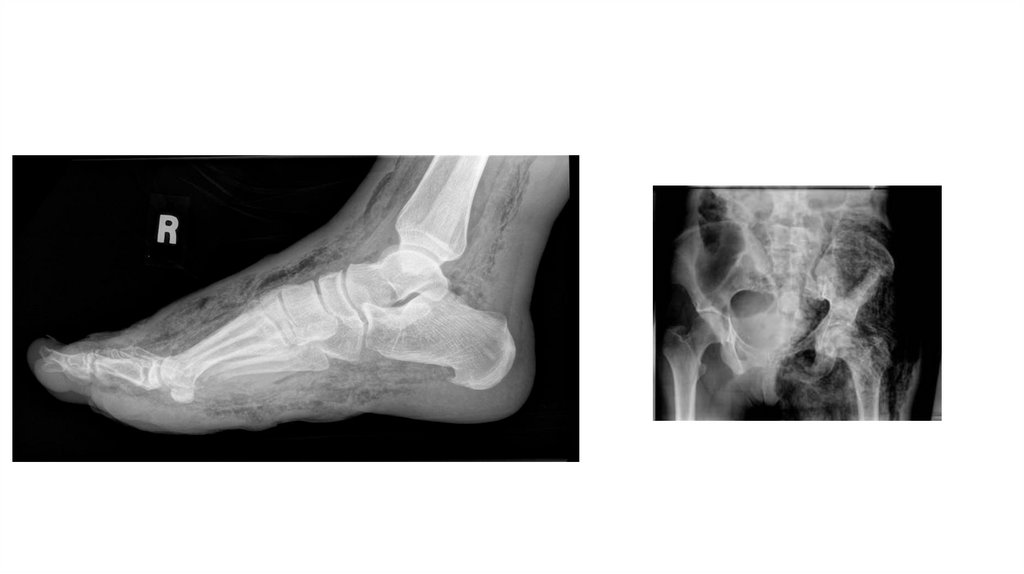

Воспалительные заболевания опорнодвигательного аппарата

«Воспалительные

заболевания опорнодвигательного аппарата»